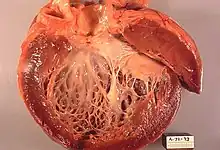

Alcoholic cardiomyopathy (ACM) is a disease in which the long-term consumption of alcohol leads to heart failure.[1] ACM is a type of dilated cardiomyopathy. The heart is unable to pump blood efficiently, leading to heart failure. It can affect other parts of the body if the heart failure is severe. It is most common in males between the ages of 35 and 50.

Alcohol-induced cardiac toxicity (AiCT) is characterized as either acute or chronic. It is believed that consumption of large amounts of alcohol leads to cardiac inflammation, which can be detected by finding large amounts of troponin in the serum.[7] Chronic consumption of alcohol (defined as greater than 80 g per day for at least 5 years) can lead to multi-organ failure, including myocardial dysfunction.[7] The exact pathophysiologic mechanism by which chronic consumption of alcohol causes DCM is not well understood, however it's believed that genetic mutation, and mitochondrial damage due to oxidative stress injury may play a role.[7]

Abnormal heart sounds, murmurs, ECG abnormalities, and enlarged heart on chest x-ray may lead to the diagnosis. Echocardiogram abnormalities and cardiac catheterization or angiogram to rule out coronary artery blockages, along with a history of alcohol abuse can confirm the diagnosis.[4] It's important to note that part of diagnosing Chronic ACM is noting the absence of coronary artery disease.[7] It's also worth noting that the diagnosis of ACM is largely a diagnosis of exclusion.